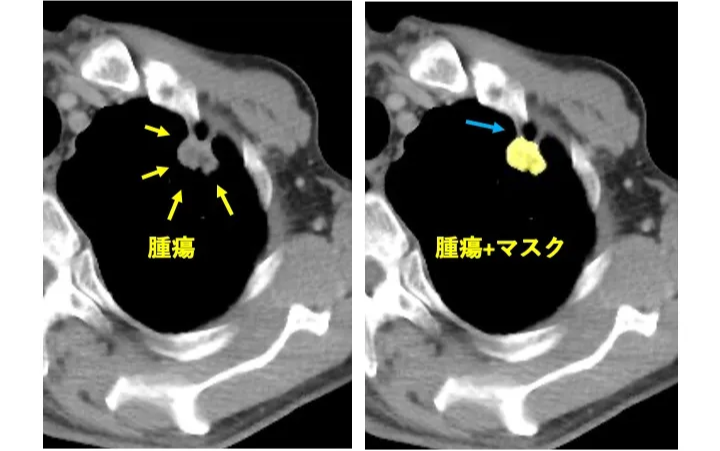

領域抽出について

腫瘍の領域抽出は専門医による手動作成が一般的ですが、本検討では、MedSAM2を用いた半自動抽出によって行いました。これによりマスク作成を効率化できましたが、一部の症例で抽出不良を確認しました。特に、腫瘍辺縁を正確に捉えていない場合があり、形状の歪みや辺縁の不整性を表す特徴量において寄与度を下げた可能性があります(Fig.7)。このことから、今後抽出精度の向上が必要と考えます。

辺縁を十分に捉えきれていない部分(水色矢印)が観察できる。「転移あり」の本症例は「転移なし」と予測された。